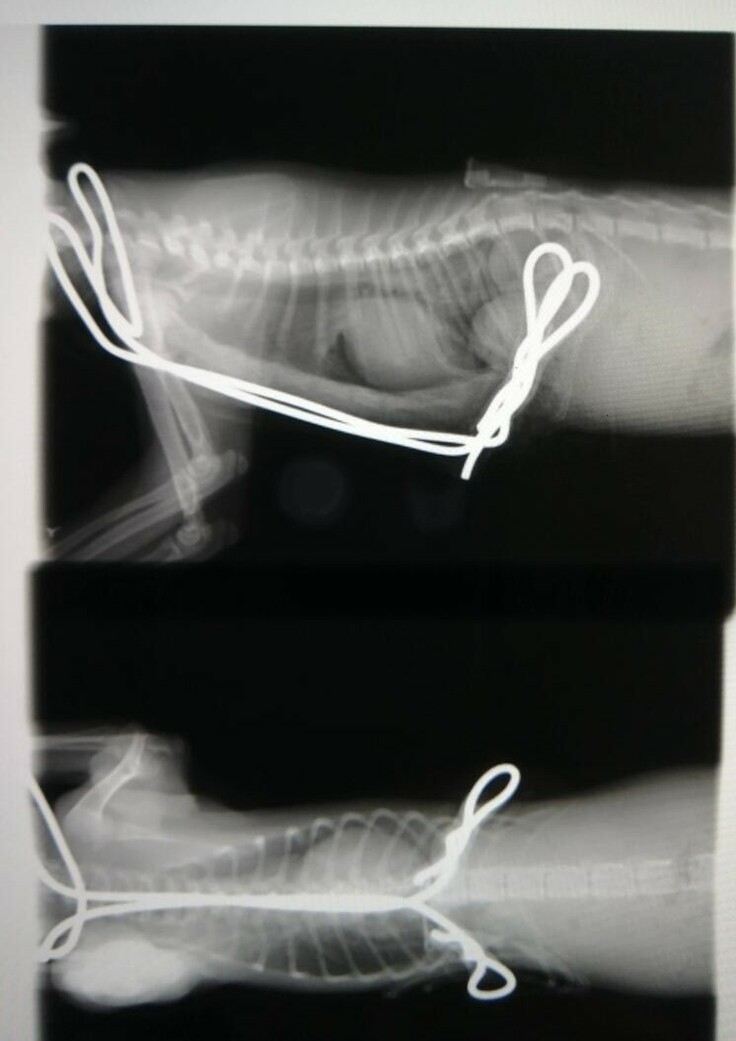

これは横からみた、レントゲンの写真です。

心臓の手前のみぞおちの胸骨が背骨側にへこんでいます。

心臓よりも右側で背骨がくいっと右上に曲がったところですが、

臓器が本来の位置より左側にずれてヘルニアになっています。

心臓も普通は肋骨2個分ですが、3個分に肥大しています。

心臓エコーもしましたが、右心室が委縮していました。

これは、上から見たレントゲンの写真です。

心臓の位置も、本来は真ん中ですが、 大きく右にずれています。

気管支も肺もずれているのでしょうか。

固定器具はワイヤーとテグスを用いたもので処置していただきました。

肋骨の固定器具は1~2か月間、体内外に残置され、治療もしばらく継続されます。